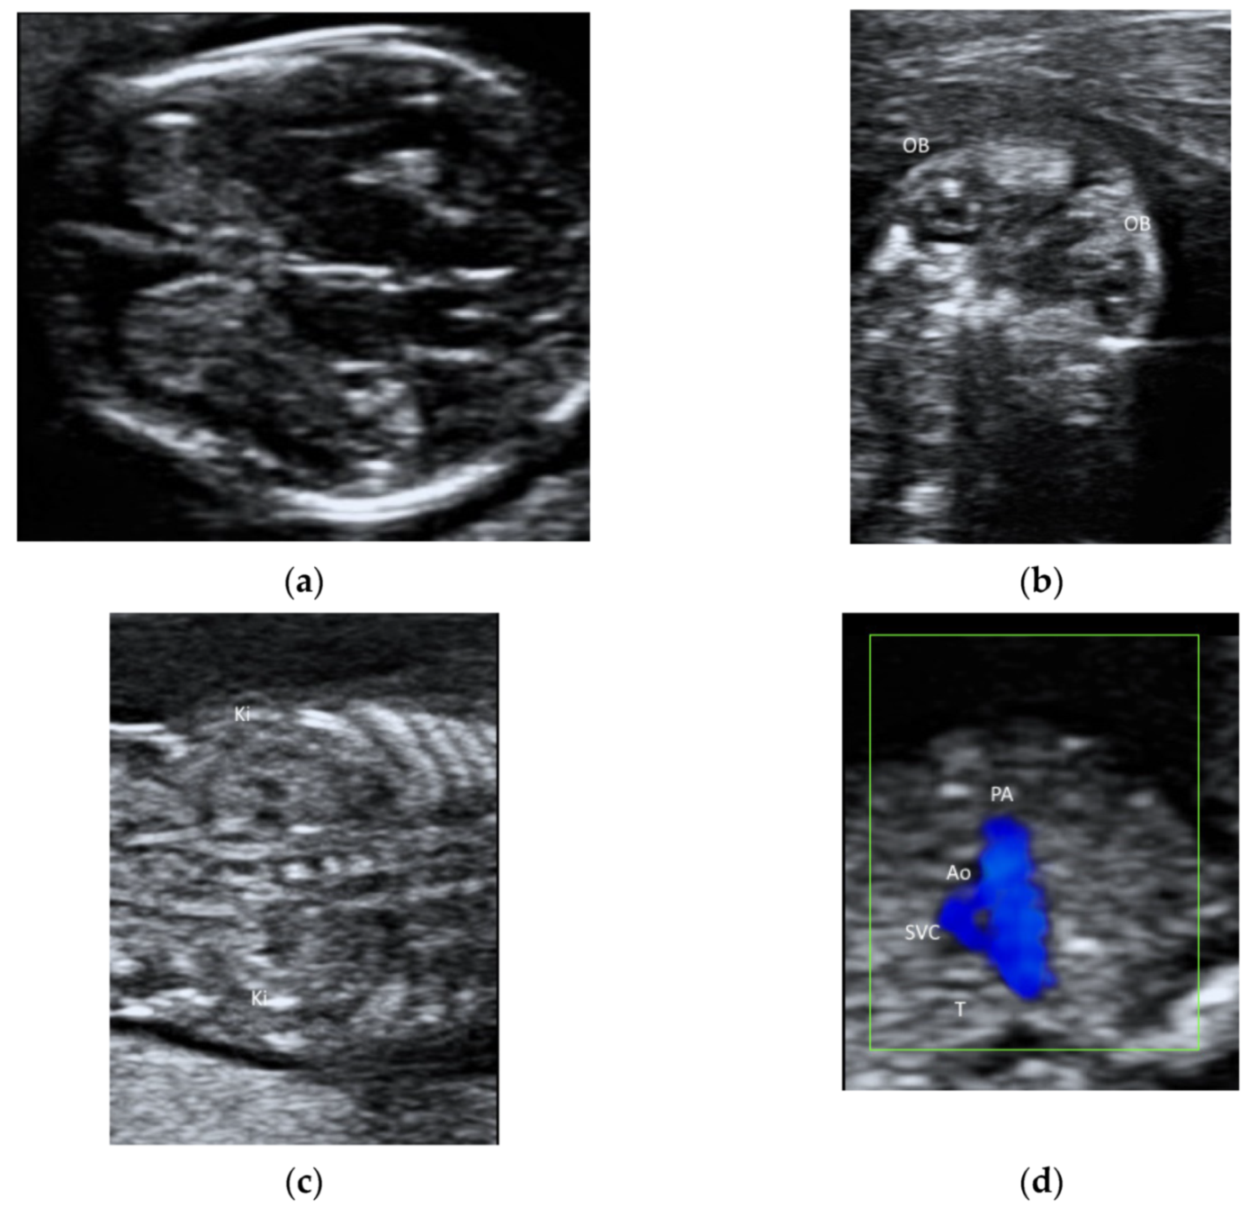

A linear transducer can be used to examine fetal structures in the first trimester (Figure 6a–d). However, a linear transducer is not suitable for using if the structures of interest are deep or the maternal abdominal wall is thick. Although a linear transducer can allow the examination of the fetal cardiac anatomy at 11–13 weeks [40], it is the use of color flow mapping but not of a linear transducer that improves the examination [41].

Figure 6.

Ultrasonography of a fetus at 13 weeks’ gestation by a transabdominal high-frequency linear transducer: (a) transverse view of fetal brain, (b) coronal view of face showing both orbits (OB), (c) coronal view of abdomen showing both kidneys (Ki) on either side of the spine, and (d) the three-vessel trachea transverse view with color Doppler showing pulmonary artery (PA), aorta (Ao), superior vena cava (SVC), and trachea (T).